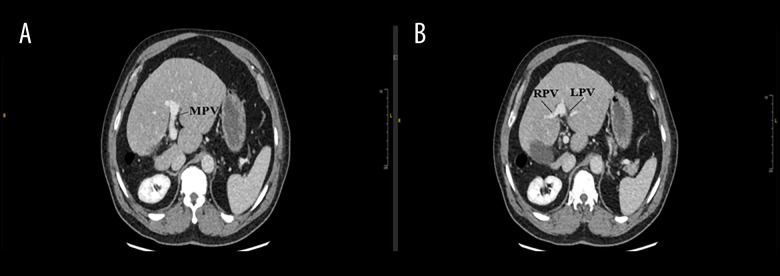

背景右肝叶发育不全是一种罕见的先天性异常,通常在影像学或外科手术中偶然发现。这种异常在手术中可能具有挑战性,导致术中并发症。右肝发育不全患者通常生活正常,无症状,但可合并肝硬化、门静脉高压症和胆结石。虽然先天性肝发育不全和胆囊炎之间的确切病理生理关系尚不清楚,但已经提出了一些促成因素。这些包括肝细胞核因子1B (HNF1B)转录的突变,胆囊功能受损以及由于位置不当导致的胆囊缺血。病例报告:一名70岁男性表现为坏疽性胆囊炎并并发右肝叶发育不全;以前没有记录的组合。患者最初无症状,表现为剧烈的胃脘痛,经腹部超声诊断为急性胆囊炎。然而,计算机断层扫描(CT)成像显示右肝叶严重发育不全,伴有左肝叶代偿性肥大,胆囊结石。尽管实验室结果正常,但我们认为这种异常延迟了诊断,直到发展为胆囊炎作为并发症。患者接受了成功的腹腔镜胆囊切除术,没有转到开放手术。结论:本病例强调了在计划手术时识别解剖变异的重要性。意识到右肝叶发育不全有助于及时诊断和适当处理,最终减少手术风险和并发症。此外,我们建议在急性胆囊炎症状不明确或不典型的情况下,以及腹部超声(US)显示胆囊位置异常时,进行CT检查。然而,我们建议在手术中确定解剖结构,以避免并发症。

BACKGROUND Hypoplasia of the right hepatic lobe is a rare congenital anomaly often discovered incidentally during imaging or surgery. This anomaly can be challenging during surgery, leading to intraoperative complications. Patient with right hepatic hypoplasia usually live normally without symptoms, but it can be associated with liver cirrhosis, portal hypertension, and gallstones. While the exact pathophysiological relationship between congenital hepatic hypoplasia and cholecystitis remains unclear, a few contributing factors have been proposed. These include mutations in the hepatocyte nuclear factor 1B (HNF1B) transcription, impaired gallbladder function, and gallbladder ischemia due to malposition. CASE REPORT A 70-year-old man presented with gangrenous cholecystitis and concurrent hypoplasia of the right hepatic lobe; a combination not previously documented. The patient, initially asymptomatic, presented with sharp epigastric pain and was diagnosed with acute cholecystitis through abdominal ultrasound. However, computed tomography (CT) imaging showed severe hypoplasia of the right liver lobe with associated compensatory hypertrophy of the left lobe in addition to stones in the gallbladder. Despite normal laboratory results, we think that the anomaly delayed the diagnosis until the development of cholecystitis as a complication. The patient underwent a successful laparoscopic cholecystectomy without converting to open surgery. CONCLUSIONS This case underscores the importance of recognizing anatomical variations when planning surgery. Awareness of right hepatic lobe hypoplasia can aid in timely diagnosis and appropriate management, ultimately reducing surgical risks and complications. Furthermore, we recommend performing CT in case of vague or atypical symptoms of acute cholecystitis, as well as when the gallbladder shows malposition on abdominal ultrasound (US). However, we recommend identifying the anatomical structure during the surgery to avoid complications.